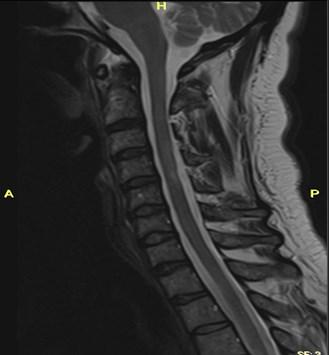

World Hypertension Day is celebrated on 17 May 2024, another important day on the health calendar. But what is hypertension and what is the buzz all about?

Blood pressure is literally the force of blood pushing against the walls of blood vessels and is measured using a blood pressure cuff. Hypertension occurs when the blood pressure through these veins is high.

What is normal blood pressure?

A normal blood pressure reading is less than 140/90 mmHg, and hypertension is defined as blood pressure more than 140/90 mmHg.

Symptoms:

Maj (Dr) Marie Schuster from 3 Military Hospital’s Family Medicine Department, says that people with very high blood pressure (180/110 or higher) can experience symptoms including headaches, chest pain, dizziness, buzzing in the ears,

World Hypertension Day

What is a hypertensive crisis?